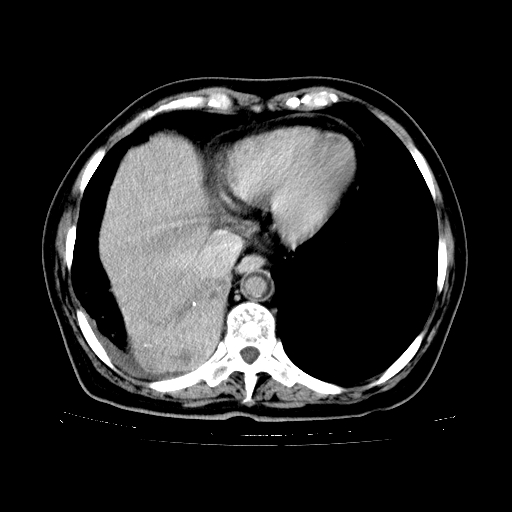

女,70岁,咳嗽、咳痰一个月,低热一周。

3、两肺肺结核(右肺下叶背段及左肺)。